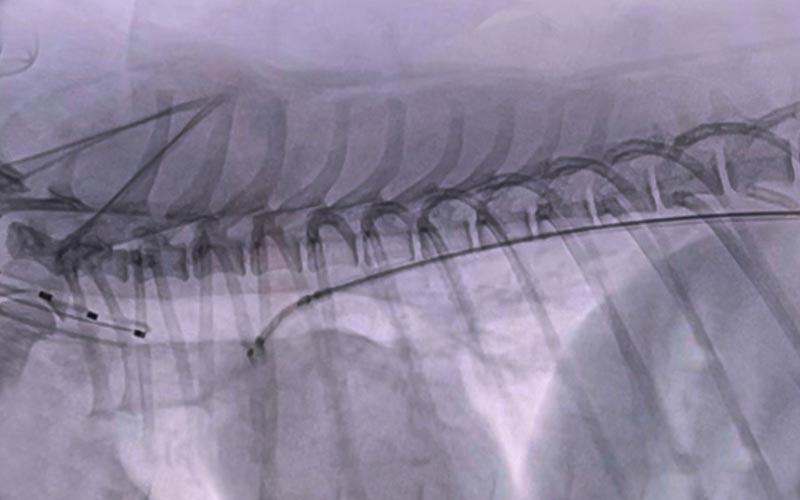

요도폐색 (Urethral Obstruction)

스텐트 삽입술 (요로 개방 유지)

• 인터벤션방식으로 조직 손상이 거의 없음

• 빠른 요로 흐름 회복으로 통증·신장 손상 감소

• 기존 수술 방법에 비해 재발·협착률 감소 효과 기대